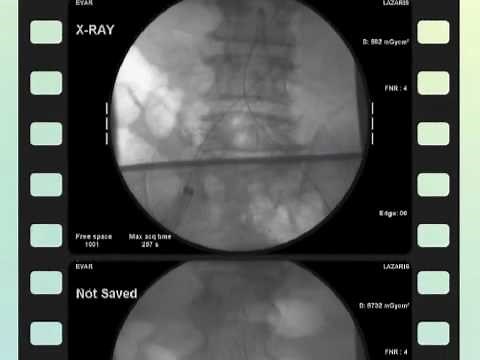

Endoleaks after Endovascular Rep…